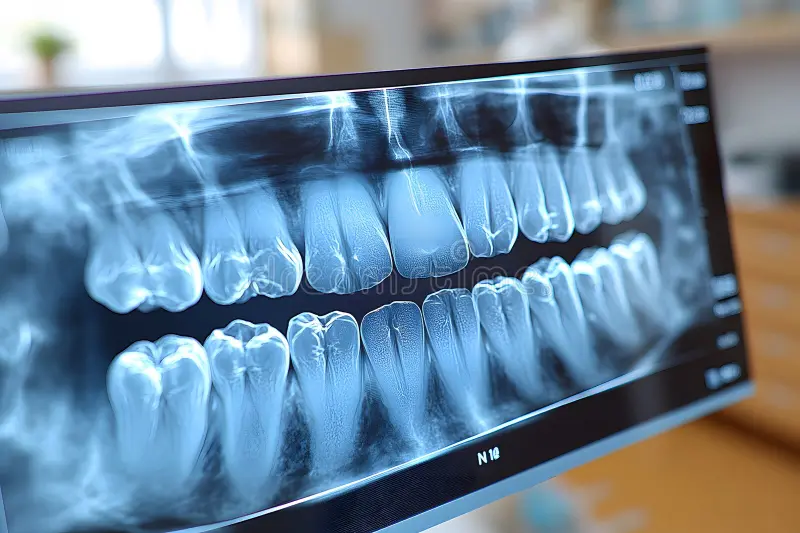

At At Grand Avenue Family Dental in Surprise, AZ your safety and comfort are our top priorities. That’s why we use advanced digital X-ray technology to get a clear, detailed look at your teeth and jaw while exposing you to significantly less radiation than traditional X-rays—up to 90% less. Digital X-rays are fast, safe, and comfortable. They help us detect cavities, bone loss, infections, and other dental issues early—often before you feel any symptoms. Images appear instantly on our screen, so we can review them with you in real time and explain any findings. We work closely with your implant provider to ensure a smooth, successful restoration process. We also offer flexible payment plans and accept most dental insurance plans to make your dental treatment restorations more affordable.